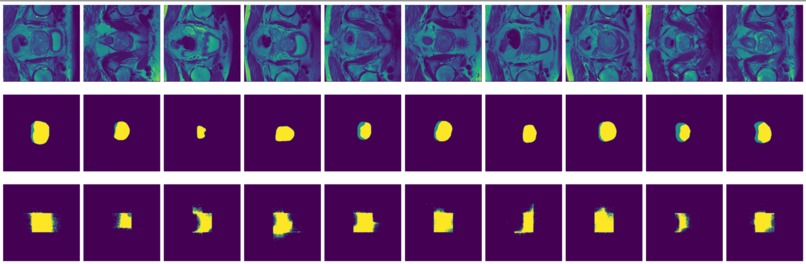

Figure 3: MRI slices (first and thrid rows) from one study with labels (second and fourth rows).

The prostate data set was acquired at Radboud University Medical Center, Nijmegen Medical Centre, Nijmegen, The Netherlands. It consists of 48 prostate multiparametric MRI (mpMRI) studies, 32 of them have corresponding region-of-interest (ROI) targets (background= 0, TZ= 1 and PZ= 2). Each study contains approximately 15 to 20 slices of MRI images, resulting in 602 images in total. Figure 3 shows the 20 slices from one study. The first and last few MRI slices contain little segmentation information. Therefore, to simplify the problem, we will discard the first and last 5 MRI slices from each study. We will use 10 studies (95 images) as the test set and the remaining 22 studies (187 images) as the training set.